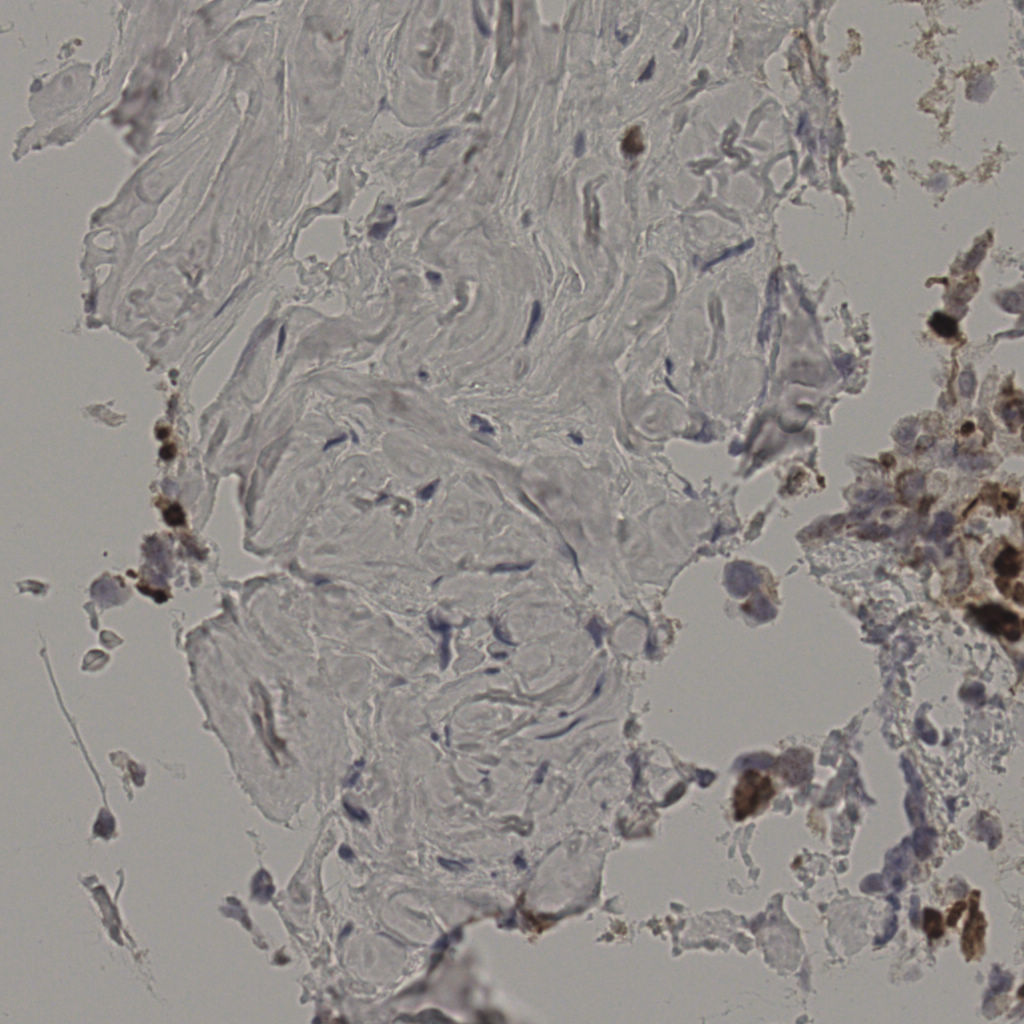

17.75%

Ki67 指数

阴 7986 阳 1723

20240285Ki-67.ndpi